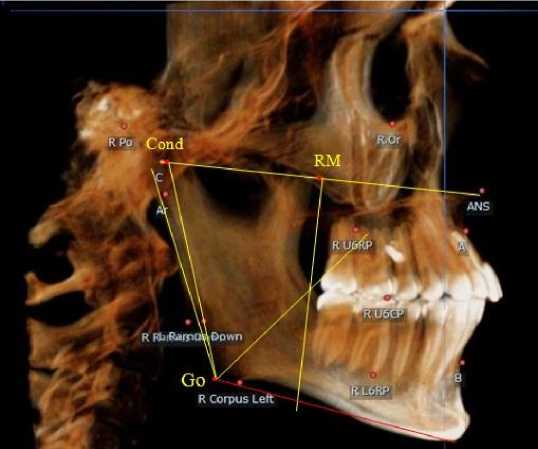

Основу анализа телерентгенограмм составляла кондиллярно-спинальная линия, соединяю- щая верхнюю точку суставной головки с передней носовой остью (Cond-SNA). На середину указанной линии ставили точечный ориентир (RM), от которого вниз проводили перпендикуляр, который, так же, как и на ортопантомограмме, ограничивал ретро молярную область (рис. 2).

Рис. 2. Анализ боковой телерентгенограммы (а) и 3D-модели (б) в периоде сменного прикуса

Стресс-осью для оценки положения нижнего дистального зуба (или зачатка зуба) служила биссектриса кондилярно-гониально-ментального угла ( Cond-Go-Ме ), в отличие от аналогичной оси ортопантомограммы.

При анализе боковых телерентгенограмм и трехмерной модели установлено, что положение зубов и челюстей относительно реперных линий было близким по значениям, полученным при анализе ортопантомограмм.

На середину суставной горизонтальной линии Cond-SNA ставили точечный ориентир ( RM ), от которого вниз проводили перпендикуляр, который, так же, как и на ортопантомограмме, ограничивал ретромолярную область. Зачаток первого верхнего постоянного моляра, как правило, располагался впереди ретромолярной вертикали.

Биссектриса угла Cond-Go-Ме (стресс-ось), так же, как и на ортопантомограмме, располагались позади от формирующихся зачатков первых постоянных моляров нижней челюсти (рис. 4).

Таким образом, для анализа положения зубов и оценки соразмерности челюстей в клинической практике приемлемы оба анализа рентгенограмм как ортопантомограмма, так и боковая телерентгенография.